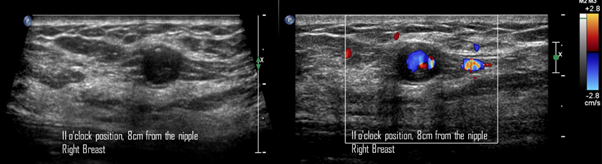

49-year-old women was diagnosed with palpable and suspicious nodule of right breast. Therefore, a core needle biopsy by ultrasound-guided was performed. The pathological report reveals a benign nodule. Two days after percutaneous biopsy, she attends to our breast center due to a new and palpable nodule in the right breast. In the craniocaudal and electronical magnification projections a round, isodense and circumscribed nodule is found in the anterior third of outer quadrant of the right breast (Figure 7). By ultrasound, a round, circumscribed, thin-walled nodule, with internal echoes is visualized in the right breast at 11 o'clock position, 8cm from the nipple, adjacent to the biopsy site. Color Doppler shows the Yin-Yang sign at the center of the nodule (Figure 8). We explained to the patient about the therapeutic options and collateral effects; however, she rejected treatment for PSA. In subsequent mammography projections, the PSA starts to appear like a hypodense nodule with increased microcalcifications within it, until a microcalfication completely covers the nodule. Meanwhile, on gray-scale ultrasound images, periodically, the nodule is filled with microcalcifications. Using color Doppler, the nodule is seen with less internal vascularity until it becomes avascular. This description corresponds to a PSA with spontaneous thrombosis after 7 years of the diagnosis (Figure 9).

Figure 8 A) Gray-scale ultrasound image. A round, circumscribed, thin-walled nodule, with internal echoes is visualized in the right breast at 11 o'clock position, 8cm from the nipple, adjacent to the biopsy site. B) Color Doppler image. The Yin-Yang sign is present at the center of the nodule.